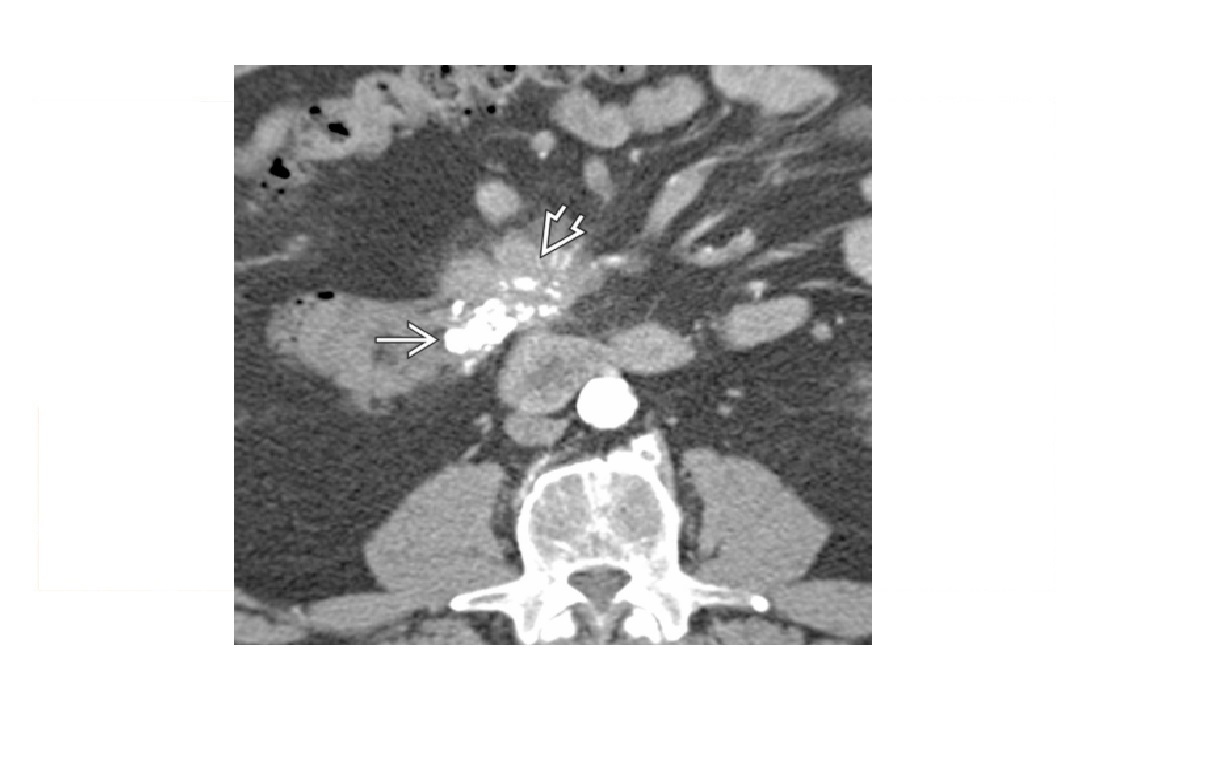

Carcinoid

spiculated mesenteric mass with calcification/ desmoplastic reaction

Tethering of SB loops

90% arise in terminal ileum/appendix

Hyper-vascular liver mets - Carcinoid syndrome

111I- Octreotide scans (1st - highest sensitivity)

or 123I-MIBG (for 10% dont take up octreotide)

for Dx and staging

Big centres use gallium PET

Assocaited with MEN 1 or MEN 2a